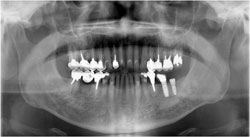

50歳代 男性 初診時のレントゲンです。

下の左側(画像では右下)にインプラントを埋入します。

施術前の診断です。

どのくらいの長さのインプラントを用いるかを測定を行います。